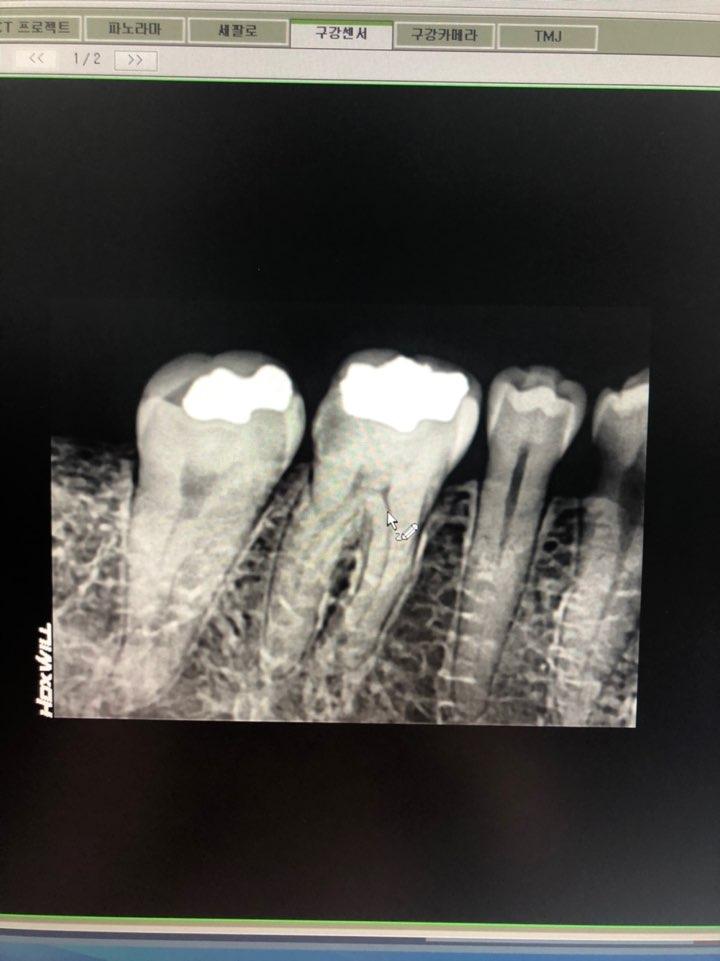

어제 2월사진과 비교해보라고 조언해주셔서 사진은찍어왓어요 혹시 한번 봐주실래요 ㅠㅠ아래가 오늘찍은거고 위가2월달에 찍은거요 ..문제는 다른치과에서 치료하면 다시 60만원을 다 내야하고 ㅠㅠ양심치과에서 as해주면 좋을텐데 말이나 해볼려고 하는데 머라고 해야할지도 모르겠고